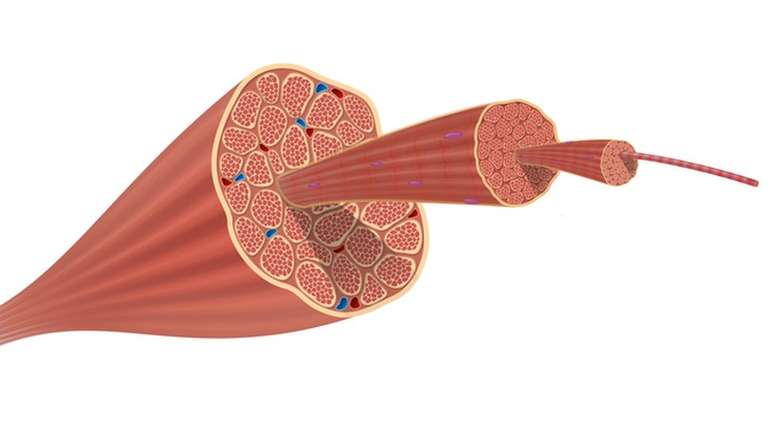

O músculo nada mais é do que um conjunto de fibras, que se deslizam umas sobre as outras em movimentos de contração e relaxamento.

Como ilustrado na imagem, o músculo reúne um conjunto de fibras que se contraem e relaxam para permitir certos movimentos